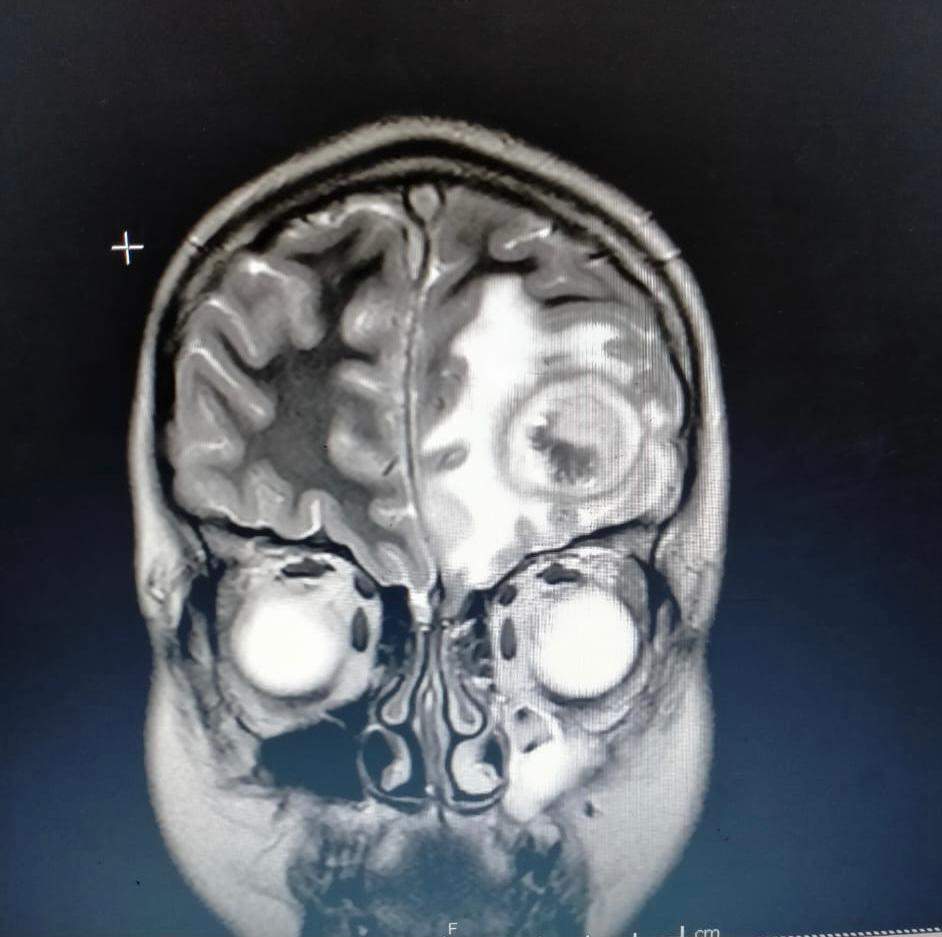

وأكد مدير مستشفى الأطفال أن الطفلة جاءت إلى المستشفى والتشخيص لحالتها كان في البداية غير مفهوم ولكن بعد الفحوصات وتشكيل فريق طبي، وعمل رنين تبين أن الطفلة لوما تعاني من ٢ خراج على المخ وخراج على الرئة وتسمم في الدم .

وقال مدير مستشفى الأطفال: الحمد الله اجتهادنا كفريق طبي مكون من الدكتورة ميادة عاطف، تخصص أمراض معدية وفريق من الجراحين قام بتفريغ الصديد من المخ وخرجت لوما من المستشفى، والحمد لله كتب الله لها الشفاء.